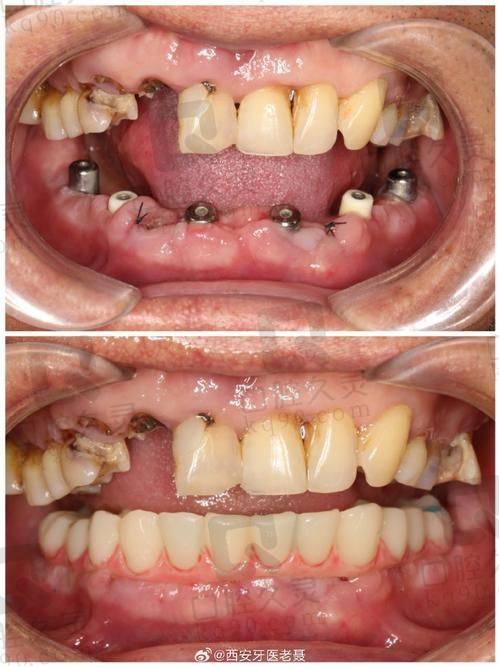

毕节盛华口腔医院以其创新的治疗项目和个性化服务理念,成为患者的优选。医院提供即刻种植牙、美白瓷贴面、美学修复等特色治疗,每位医生都会根据患者的具体情况,制定个性化的治疗计划。